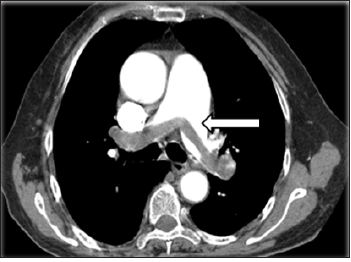

A previously healthy 46-year-old man was admitted because of sudden-onset syncope 8 hours previously. The patient had suddenly fainted 8 hours prior to presentation with no known cause and lost consciousness; however, he had no convulsions of any limbs and no fecal or urinary incontinence. The syncope lasted for about 3 minutes, and the patient gradually regained his consciousness accompanied by shortness of breath, chest distress, coughing, and expectoration. Examination upon admission revealed type I respiratory failure, and Computed Tomography (CT) pulmonary angiography showed an embolism in the main pulmonary artery; however, ultrasound examination showed no thrombus in the lower extremities (Figure 1). On physical examination, the patient’s blood pressure was 98/45mmHg, his lips were cyanosed, his heart rate was 115beats/min with a regular rhythm, and his respiratory rate was rapid (about 30breaths/min) with coarse respiratory sounds in the bilateral lungs. No swelling was seen in the lower limbs. After admission, blood gas analysis (mask-delivered oxygen at 5L/min) showed the following: pH, 7.30; PO2, 45.40mmHg; PCO2, 36.50mmHg; and SO2, 85.8%. His D-dimer concentration was 3.75mg/L. After treatment with oxygen inhalation, the patient was able to assume a supine position. His PE severity index was 126 points (grade V is defined as >125 points, which indicates very high 30-day mortality risk of (10.0-24.5) %.

Figure 1:Preoperative computed tomography showed thromboembolism in the bilateral main pulmonary arteries (arrow).